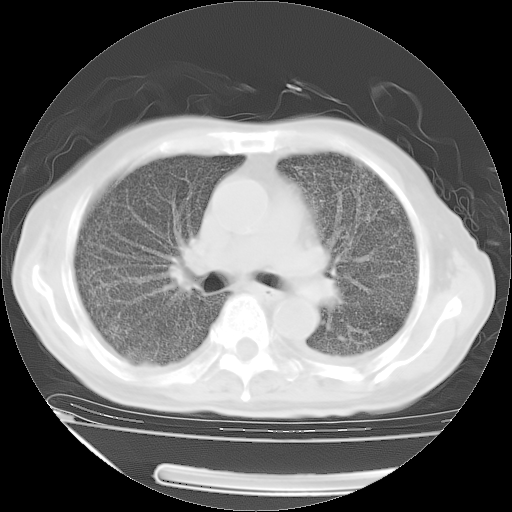

甲强龙80mg/日+抗结核治疗(异烟肼+利福霉素+乙胺丁醇)10天。复查肺部CT。

治疗10天肺部CT